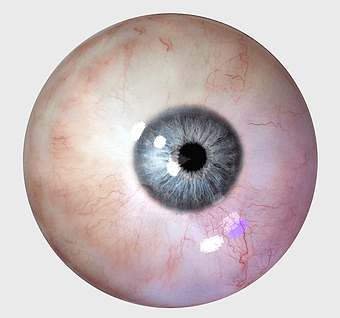

Human eye closeup, iris and sclera details, ophthalmology stock image, eye organ anatomy, ocular health, visual system study, eye texture analysis -

Human eye cornea, visual perception closeup, eye examination details, iris color analysis, ocular health, eye anatomy illustration, corneal structure view -

blue iris closeup, human eye pigment, visual perception organ, eye color analysis, ocular anatomy details, iris texture patterns, eye health examination -